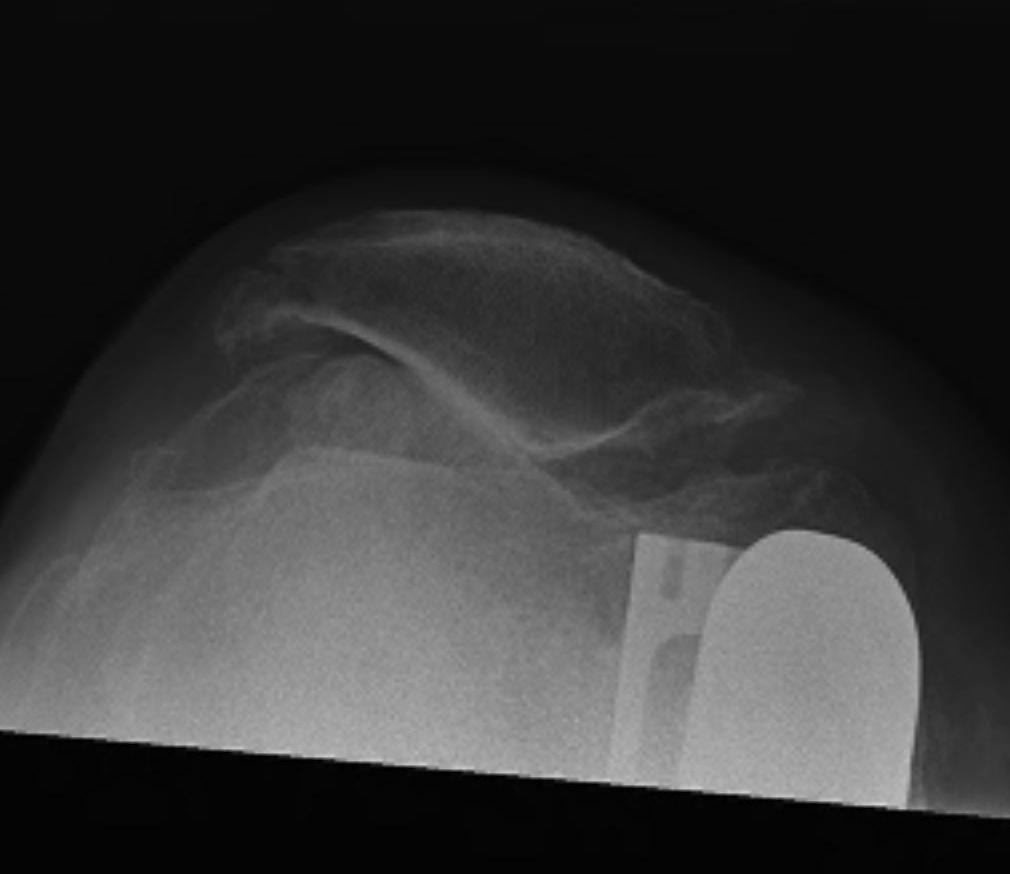

AP / Lateral / Skyline

Patient 1